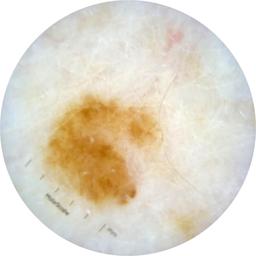

ISIC_6708537

acquisition_day 525

age_approx 70

anatom_site_1 Upper extremity

diagnosis_1 Benign

diagnosis_confirm_type single image expert consensus

fitzpatrick_skin_type I

image_type dermoscopic

personal_hx_mm True

sex female